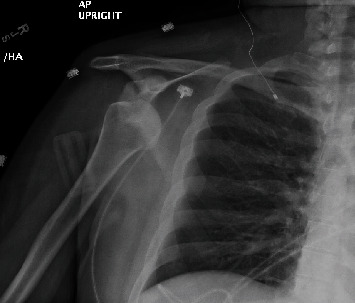

Dislocation of the glenohumeral joint secondary to generalized tonic-clonic seizures is well documented in the medical literature, with posterior dislocation being most commonly described. Still, these occurrences tend to be rare and affect a minority of patients, and fractures associated with dislocations after seizures are even less common. As such, the management of these injuries tends to be quite varied, and there is a paucity of documented cases in the literature. Here, we would like to present two rare cases of anterior shoulder dislocation secondary to seizures, with one patient also sustaining a fracture of the proximal humerus. We would also like to discuss the management and outcomes that have been achieved, since these cases tend to occur in a small number of epileptic patients.